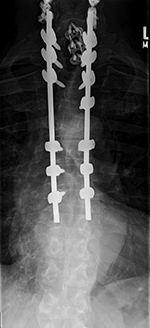

| Occiput-T8 posterior fusion with anterior cervical fusion from C6-T1. |

| 59 year-old man with occiput to T8 posterior fusion. There is anterior cervical fusion from C6-T1. PEEK disk cages are present at C6-7 and C7-T1. An old compression fracture is present at T5. In the cervical spine lateral mass screws are at C3-6 bilaterally. In the thoracic spine pedicle screws are at T1-3 and T6-8 on the right and at T1-4 and T6-8 on the left. Laminectomies have been performed from C3 to C6. |